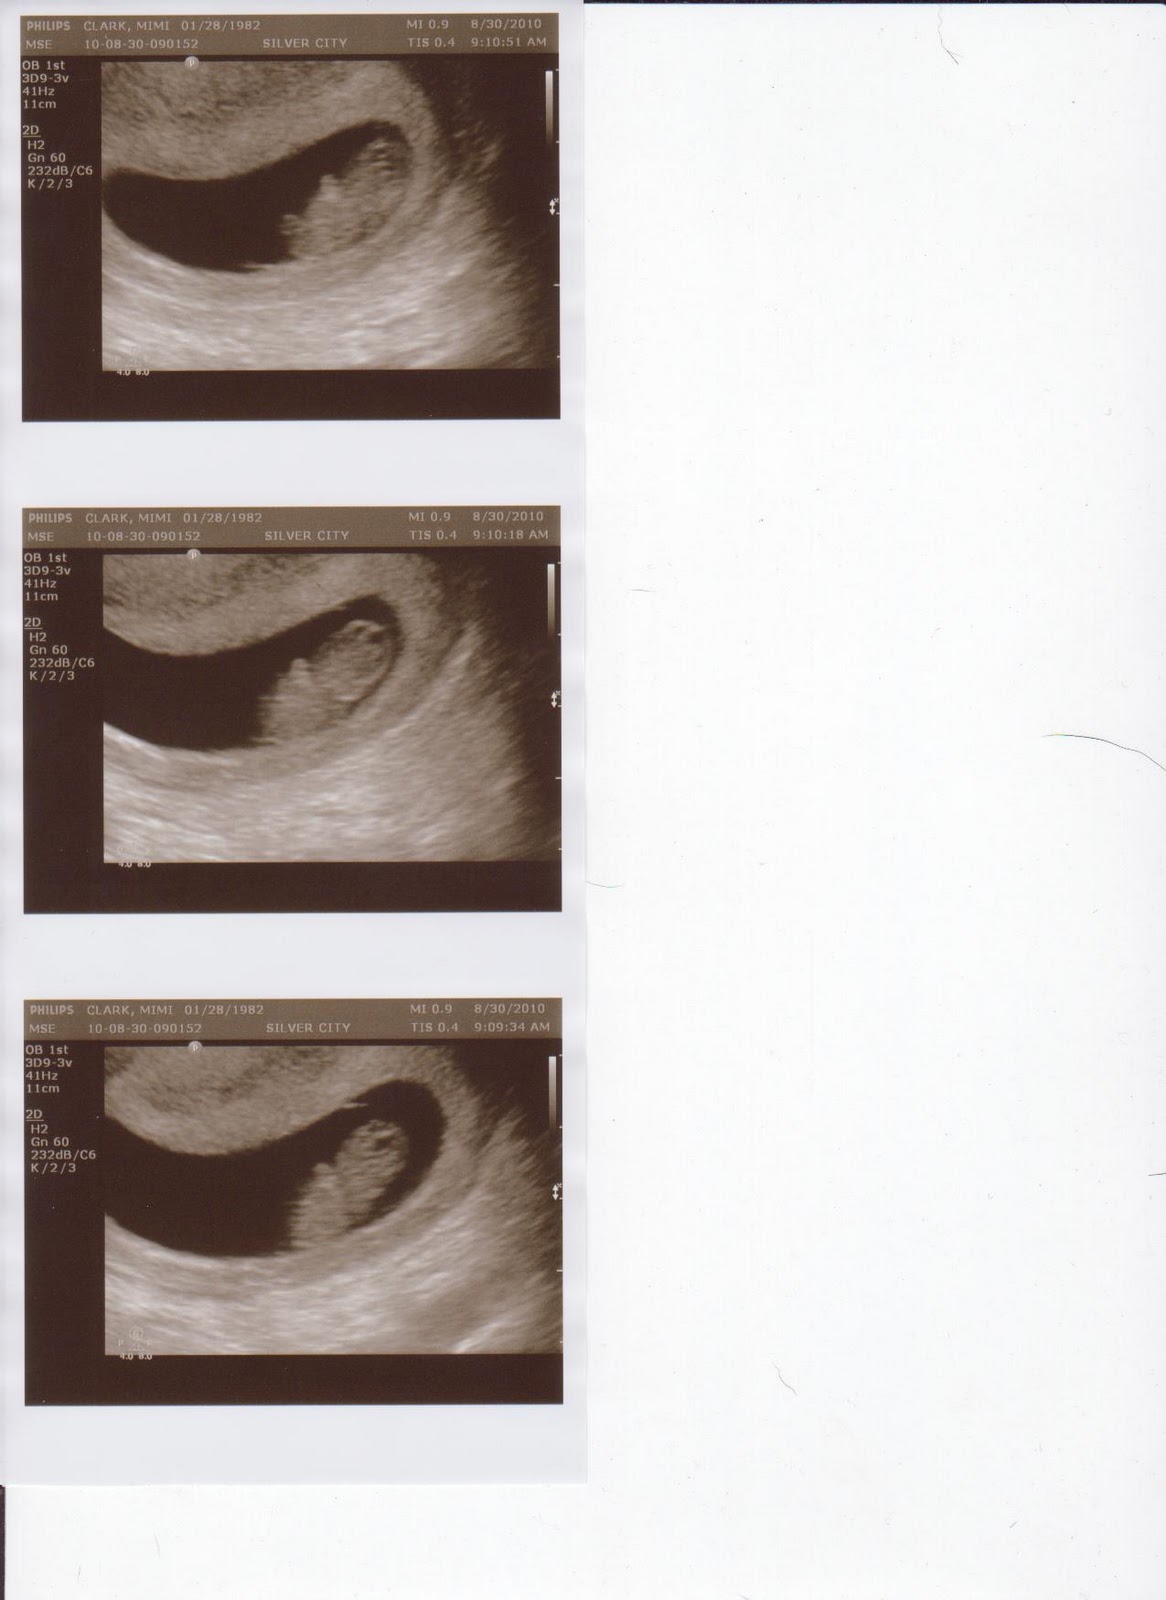

When we went to the doctor I was told to come with a 1/2 bladder. As I sat down in the chair with Adam holding my hand I was very nervous. Since my only real symptoms of pregnancy were huge boobs and cry baby I kept second guessing myself if I were even pregnant. I laid there in anticipation as she put the little wand on my belly. Nothing was there. I got nervous and asked her if I was supposed to see something and she said well why don't you empty your bladder and come back. In the bathroom I was sweating. I was starting to think I either had a miscarriage or was faking the whole thing. When I came back she took a different approach...up the vag. The ultrasound technician explained to me that I had an tilted uterus, which 1 out of every 2 people had. I really could have cared less though as my eyes were scanning the screen to make sure something was there. Finally, after what seemed like hours, we finally saw our little baby.

It was so exciting and amazing. He/She looked like a little gummy bear and was so adorable. The little bear was moving around like crazy and fist pumping and dancing all over the place. Adam teared up a little and was excited to see something finally in there! It was definitely a nice reassurance to make sure the baby was still in there. They took lots of measurements and we got to watch it dance a little more before it was over. The doctor provided my official due date which is 4/7/2011.

| First Ultrasound-8 weeks |